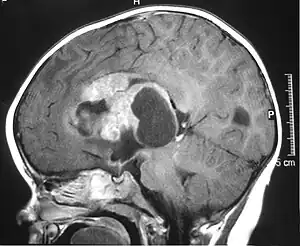

Appearance on radiologic exam

AT/RTs can occur at any sites within the CNS; however, about 60% are located in the posterior fossa or cerebellar area. The ASCO study showed 52% posterior fossa; 39% sPNET; 5% pineal; 2% spinal, and 2% multifocal.[1]

The tumors' appearance on CT and MRI are not specific, tending towards large size, calcifications, necrosis (tissue death), and hemorrhage (bleeding). Radiological studies alone cannot identify AT/RT; a pathologist almost always has to evaluate a brain tissue sample.

The increased cellularity of the tumor may make the appearance on an uncontrasted CT to have increased attenuation. Solid parts of the tumor often enhance with contrast MRI finding on T1 and T2 weighted images are variable. Precontrast T2 weighted images may show an isosignal or slightly hypersignal. Solid components of the tumor may enhance with contrast, but not always. MRI studies appear to be more able to pick up metastatic foci in other intracranial locations, as well as intraspinal locations.